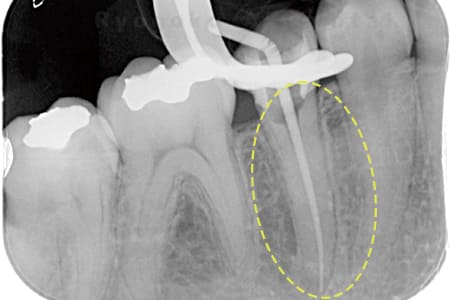

Case02

- 原因

- 慢性根尖性歯周炎

- 治療期間

- 3ヶ月

- 治療内容

- マイクロエンド

- 治療費用

- 121,000円

噛むと痛みが出る、とのことで来院した患者様です。他院での根管治療を終えてましたが、根尖病変を認めるため、マイクロエンドを行いました。

<リスク・副作用>

術後は痛み、腫れ、痺れなどの副作用が生じる場合があります。症状が再発する可能性があります。